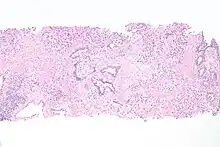

Histopathology of transitional carcinoma of the urinary bladder. Transurethral biopsy. Hematoxylin and eosin stain. | |

Transitional refers to the histological subtype of the cancerous cells as seen under a microscope.

The 1973 WHO grading system for transitional cell carcinomas (papilloma, G1, G2 or G3) is most commonly used despite being superseded by the 2004 WHO[14] grading for papillary types (papillary neoplasm of low malignant potential [PNLMP], low grade, and high grade papillary carcinoma). High-grade carcinoma typically displays more pleomorphism, multiple mitoses, euchromatin and relatively prominent nucleoli, and uneven distribution of nuclei.

- Transitional cell carcinoma, being low-grade to the left, and high-grade to the right. H&E stain

- Histopathology of urothelial carcinoma of the urinary bladder, showing a nested pattern of invasion. Transurethral biopsy. H&E stain

- Histopathology of urothelial carcinoma of the urinary bladder.